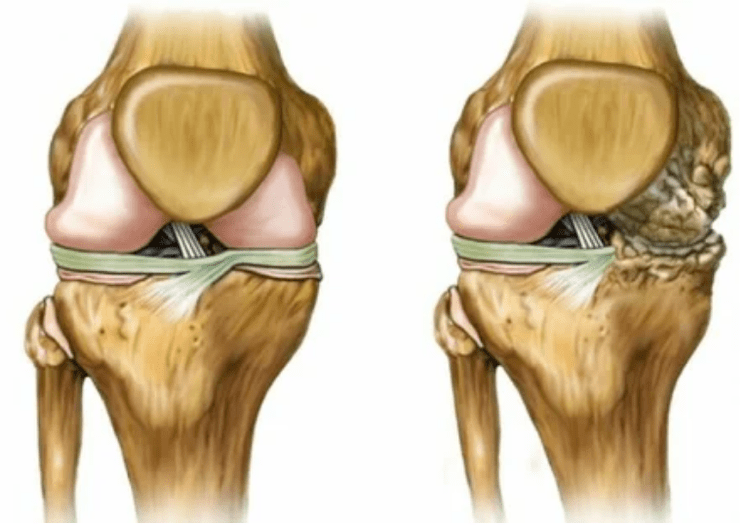

- Stage 2.Due to the supply deficiency, the necessary cartridges are destroyed, bone growths are formed on the surface of the cartilage.The pains acquire a more pronounced character, intensify after a long rest, are eliminated by small physical labor.Pain is accompanied by inflammation.The muscles are stretched, which leads to weak or average impaired motor functions.

- 3 degree.Often there are pains, it is difficult to move the limb due to changes in the joint.The lesions are extensive, become noticeable to the naked look.The deformation of the joint site occurs, the affected area swells and becomes red.The limb axis is disturbed, which leads to the complexity of movement.Pathological changes provoke shortening the ligaments.Subluishes and contractures appear.The adjacent muscles are shortened or stretched, from which the contractile function is weakened.